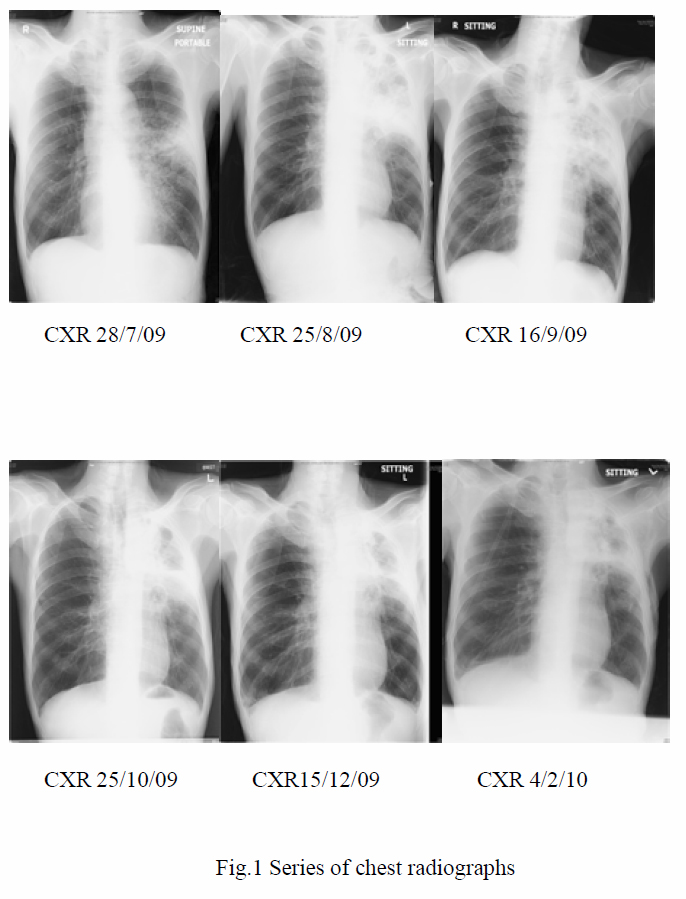

There was no recent travel or contact history. There was also no contact with animals or pets previously. He was afebrile upon admission. Chest examination revealed prolonged expiratory phase. White cell count (WCC) was 12.7x 109/L; Hb 13.4 g/dL; arterial blood gas (ABG): pH7.44; pCO2 4.45 kPa; pO2 17.86 kPa. Chest X-ray was clear. The patient was initially managed as acute exacerbation of chronic pulmonary obstructive disease (COPD) with amoxicillin/clavulanate and systemic steroids. With the subsequent development of fever, Cefoperazon/sulbactam was brought in. Sputum culture later yielded Pseudomonas aeruginosa. However, fever persisted and left middle zone consolidation increased. Antibiotics were then switched to piperacillin/tazobactam and gentamicin on 29th July 2009. Fever did not subside after the two antibiotics were given for another two weeks. Antibiotics that were subsequently employed included imipenem, clarithromycin and amikacin. Sepsis workup was repeated. Patient remained febrile with the pneumonia unresolved. Another sputum culture yielded Stenotrophomonas maltophilia in August 2009 and ticarcillin/clavulanate and co-trimoxazole were subsequently introduced according to the sensitivity profile.

In the presence of inflammatory reactions against calcium oxalate crystals on lung biopsy and the settings of unresolved pneumonia despite multiple antibiotics, the clinical diagnosis of chronic necrotizing pulmonary aspergillosis with pulmonary oxalosis was reached. Voriconazole was started on 1st October 2009. Low grade fever persisted during the first 10 days of treatment. Voriconazole was then replaced by amphotericin B, when the fever eventually subsided. C-reactive protein checked on the ninth day of voriconazole treatment later revealed marked reduction from 146.0 mg/L on 30th September 2009 to 67.7 mg/L on 9th October 2009, which was suggestive of an improvement. Voriconazole was thus resumed. The patient remained afebrile and C-reactive protein went on a downward trend. The patient was subsequently discharged with oral voriconazole. Aspergillus antibody was rechecked, which was positive after discharge. During subsequent outpatient visits, the patient remained afebrile, with improved exercise tolerance and decreased respiratory symptoms. Voriconazole was then changed to itraconazole on 1st February 2010 after cost-effectiveness evaluations. Improvement was continually noted in CRP trend, on CXRs and CT thorax with time (Fig 1, Fig 3a and 3b).

There are three clinical presentations of CNPA. Chronic productive cough is the most common feature. The second common symptom is haemoptysis, followed by constitutional symptoms like weight loss, malaise, and fatigue.10 CXR typically shows infiltrative process in upper lobes or superior segments of the lower lobes.9 A fungal ball may be seen, with adjacent pleural thickening which can vary from several millimeters to 2 centimeters.9,10 Nearly all patients with CNPA have Aspergillus fumigates precipitins in blood. Yet, the titre of antibodies varies over time and may be negative at some time in the disease course.10 Meanwhile, diagnosis is confirmed by a histological proof of tissue invasion by Aspergillus species and its growth on a culture. However, this is not always possible; so, the following criteria can be used to make a clinical diagnosis of CNPA:9